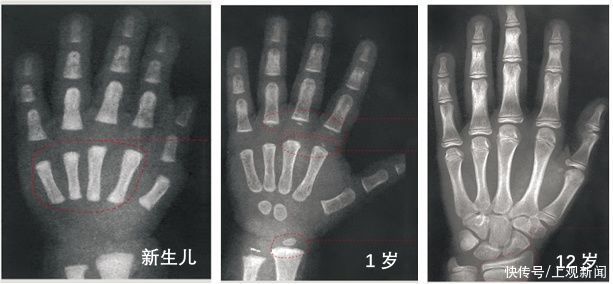

02 拍骨龄片

骨龄(bone age,BA)即骨骼年龄,是根据不同年龄各个骨化中心X线的特定图像出现时间不同来确定,其代表发育年龄,反映人体骨骼的成熟度。

一般是拍摄左手腕部加全手的X光片,观察指骨、腕骨及桡、尺骨下端的骨化中心出现的时间、面积大小,判断骨骼实际发育程度,来确定骨龄。

根据骨龄和年龄的差值来看孩子的发育程度

骨龄差在±1岁以内——正常

骨龄>年龄1岁,不超过2岁——偏早

骨龄

骨龄>年龄2岁——异常提前

举例说明:12岁的孩子,骨龄是10岁,说明发育迟缓,身体发育在正常儿童10岁的水平。